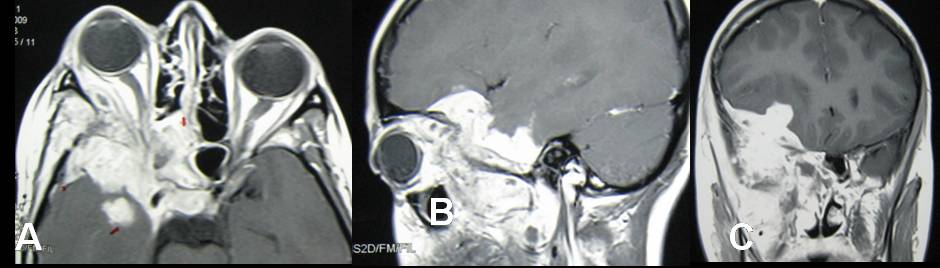

Preoperative malignant looking retrobulbar, infratemporal and middle cranial fossa tuberculoma in a young child - a case report

Tuberculosis involving skull base and brain is relatively common in developing countries. Preoperative neuro-radiological features of such lesions mimic neoplastic lesions of brain & skull base and postoperative histopathological study brings the ultimate diagnosis. Here we present a case of large tubercular lesion involving retrobulbar, infratemporal and middle cranial fossa that preoperatively thought to be a malignant lesion in a young child and was managed surgically with anti-tubercular drugs having a happy termination. Even radiologically malignant looking mass lesion in brain and skull base can be proved as tuberculosis that can bring happiness to the patient and also to the treating neurosurgeons.